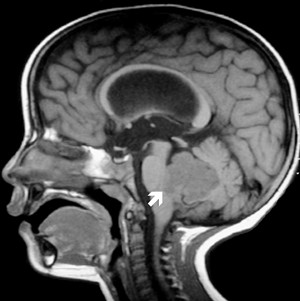

腦腫瘤是小兒時(shí)期最常見(jiàn)的腫瘤,是導(dǎo)致兒童疾病相關(guān)死亡的首要原因。以往許多研究都集中在涉及小兒腦腫瘤復(fù)雜的生物過(guò)程,但很少有人揭示microRNAs(miRNAs)在小兒腫瘤發(fā)生中可能扮演的角色。

本研究中,來(lái)自上海生命科學(xué)院和上海交通大學(xué)的研究人員,使用miRNAs芯片技術(shù)篩選了小兒腦膠質(zhì)瘤和配對(duì)的正常組織樣本中miRNAs的表達(dá)譜(生物芯片服務(wù)由聯(lián)川生物完成)。研究中共發(fā)現(xiàn)40個(gè)差異表達(dá)的miRNAs,其中miR-1321,miR-513b,miR-769-3p被首次發(fā)現(xiàn)與癌癥發(fā)生密切相關(guān)。研究人員進(jìn)一步通過(guò)qRT-PCR方法對(duì)篩選出的差異miRNAs進(jìn)行驗(yàn)證。

此外,通過(guò)對(duì)篩選的40個(gè)差異miRNA的靶基因預(yù)測(cè)以及GO和pathway富集分析表明,這些miRNAs作用的靶基因主要與神經(jīng)系統(tǒng)以及腫瘤相關(guān)的生物過(guò)程和信號(hào)轉(zhuǎn)導(dǎo)通路密切相關(guān)。

本研究為兒科腦腫瘤生物學(xué)研究提供了更好的思路,將有助于開(kāi)發(fā)小兒腦腫瘤低毒性的治療方法。同時(shí)通過(guò)miRNAs模擬物和抑制劑可以增強(qiáng)或減弱靶基因的調(diào)控,有望成為新的抗腫瘤療法。